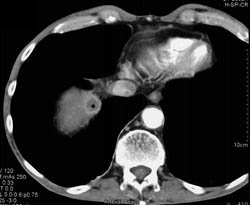

Liver Metastases